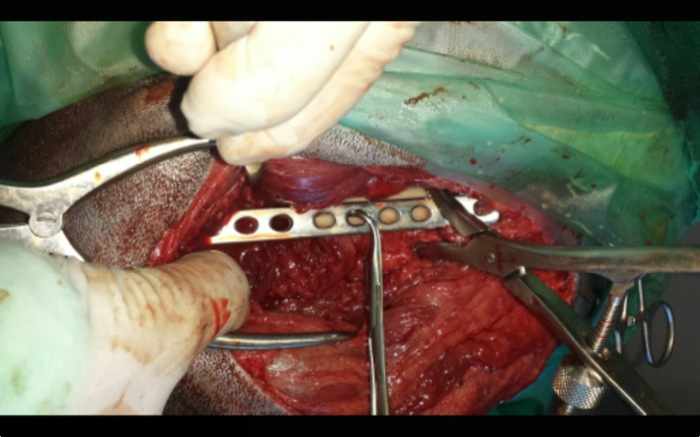

| Tratamiento | Se coloca una placa que en este caso es de 4 mm de grosor dada la fractura y el peso del animal. Previamente se fija, con alambre de 0,8 mm, el único gran fragmento musculado que impedirá complicaciones por necrosis y facilitará su osificiación. El resto aparecen totalmente sueltos y se retiran sobre todo por tratarse de fractura abierta y llevar 3 días. |

La primera parte quirúrgica, el abordaje entre bíceps femoral y tensor de la fascia, lleva más tiempo de lo habitual por la dificultad de ver claramente dada la gran inflamación. Una vez que entramos encontramos coágulos por todas partes por el estallido del hueso que rasga y perfora la musculatura periférica hasta el exterior. El cerclaje atraviesa la diálisis no fracturada.

Estos fragmentos se encuentran entre los múltiples coágulos y salen al exterior simplemente lavando abundantemente con suero, no mantenían ninguna unión al músculo y quizá alguno de ellos haya impactado con algún elemento externo.

Se opta por una placa de 4 mm de grosor que de la máxima resistencia. En alguna ocasión este material que parece irrompible se parte incluso en animales de talla reducida.

Se corta casi un centímetro de las dos puntas del fragmento proximal y se eliminan por ser las responsables de estar ante una fractura abierta, quizá estar contaminadas y tener un final tremendamente cortante. Se pierde por ello un centímetro de la longitud del fémur.